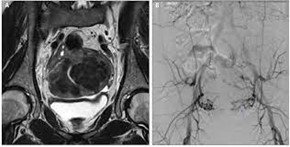

-تصویربرداری رزونانس مغناطیسی (MRI): این نوعی از فناوری تصویربرداری پیشرفته است که تصاویر بسیار دقیقی از اندام های داخلی ارائه می دهد. این تصاویر به ارائه دهنده شما کمک می کند تا محل دقیق و ویژگی های فیبروم را تعیین کند و در صورت نیاز، درمان های کم تهاجمی را برنامه ریزی کند.

-آمبولیزاسیون شریان رحمی: که آمبولیزاسیون فیبروم رحمی نیز نامیده می شود، یک روش جدیدتر است. این روش کم تهاجمی با قطع جریان خون، فیبروم ها را کوچک می کند. رادیولوژیست اینترونشنال این اقدام را با هدایت اشعه ایکس انجام می دهد. پزشک معالج برای انتخاب این روش به پیامدهای طولانی مدت این روش در مورد باروری و رشد مجدد بافت فیبروم دقت لازم را دارد.